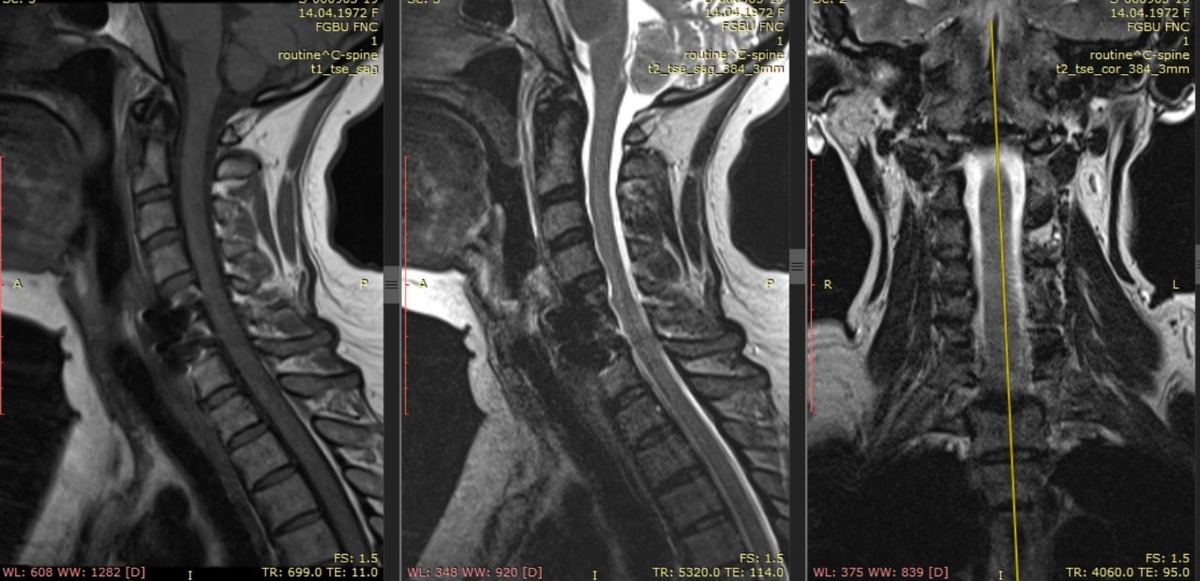

До обращения в клинику выполнены МРТ шейного отдела позвоночника и плечевого сустава слева, по данным которых не обнаружено отклонений, обуславливающих болевой синдром. В связи с тем, что пациентка не могла находиться неподвижно в положении лежа из-за выраженной боли, исследования выполнялись в условиях общей анестезии.